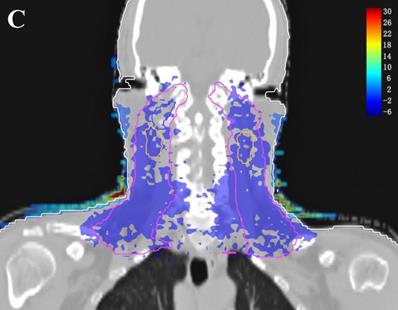

Dose difference distribution map (Plan+ - Plan-)

In the TPS, the results from two plans of the same patient can be directly subtracted to calculate the dose difference distribution map for the patient. As shown in Figure 3, the blue to red gradient represented different absolute dose difference values ranging from -6 Gy to 30 Gy. The dose distribution was dramatically altered due to the attenuation and bolus effect of the immobilization devices. In particular, as shown in B) and C), the neck dose near the head and neck immobilization device was significantly reduced, mainly due to the attenuation when the incident beam ray passes through the immobilization device. Changes in radiation scattering and build-up effect occurred due to the presence of low-density foam in the vacuum pad between the patient's neck and the floor plate. As a result, the dorsal neck skin dose was increased by approximately 10 Gy (Figure 3A, 3B).

Figure 3

Three dimensional dose difference distribution map for a typical NPC case. Dose difference was calculated through subtracting Plan- from Plan+. (A: Cross-sectional plane, B: Sagittal plane, and C: Coronal plane).

The establishment of a virtual model (including geometry and density information) for the treatment couch top within the TPS is a common method used to calculate the attenuation effect of the treatment couch on treatment planning [6,11,12]. In this study, we contoured the head and neck immobilization devices into the external body contour to calculate the immobilization device impact on the dose distribution of NPC IMRT. The density information of the immobilization devices showed the TPS calculation algorithm was able to compute dose for the situation with the immobilization devices enclosed. Due to the attenuation of the immobilization devices, CRs and Dmean in Plan+ were reduced compared to those in Plan- (the prescription dose coverage rates of the four targets were decreased by 1.5-9.9%, and the average doses were decreased by 0.9-1.9%). The attenuation effect was greater on the dose coverage rates of PTVnd and PTV2 (-9.9% and -3.6%, respectively), mainly because the two PTVs were spatially closer to the immobilization device. Table 1 showed that the Plan+ prescription dose coverage volumes for PTVnd and PTV2 were less than 95%, and according to the protocols of nasopharyngeal carcinoma IMRT planning in our center, these plans are not suitable for clinical treatment. Among the doses in OARs, except the near-maximum doses for the brain stem and spinal cord PRV had no significant difference, the average doses of all other OARs were statistically significantly reduced (with a maximum difference of 1.7%). Figure 2 showed a similar result; the DVH curves of the brain stem and spinal cord did not show significant differences between the two plans, but the curves for each PTV exhibited a certain degree of separation. The dose difference maps in Figure 3 also showed that due to the presence of the head and neck immobilization device, the dose distribution in the patient was reduced compared to that when the immobilization device was not considered. In particular, the dose in the portion of the lower neck that is close to the head and neck immobilization device was significantly reduced (most of which is in the PTVnd and PTV2 areas), mainly due to the attenuation effect of incident radiation passing through the immobilization device.